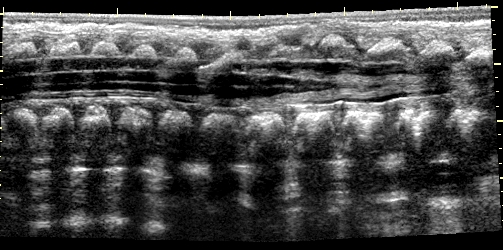

31. Normal spinal US, longitudinal view (long arrow: medullar cone, small arrow vertebral body.) Newborn.